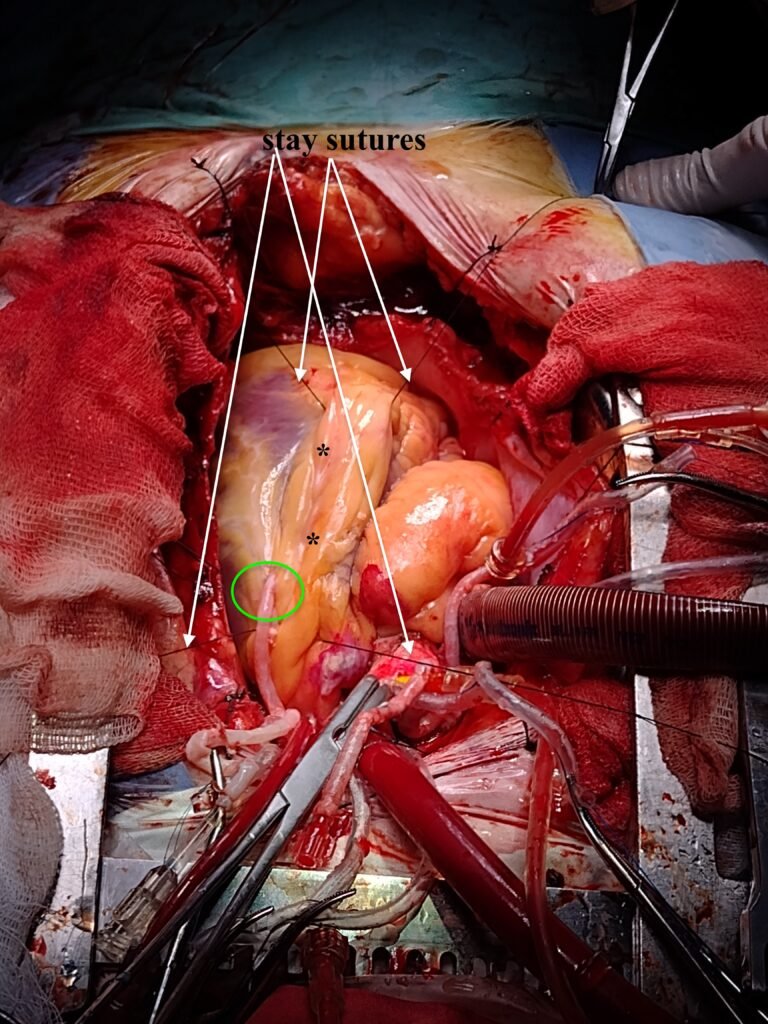

Se observa la estrategia de bypass coronario con circulación extracorpórea, en donde se utliza para inmovilizar el campo suturas (stay sutures) de seda 2-0 que pasan por el septum y señaladas con flechas blancas. Esta forma poco usual, inofensiva y altamente eficaz deja un campo quirúrgico absolutamente estable, quieto y las manos de los asistentes disponibles para ayudar en la delicada anastomosis coronaria.

Los asteriscos (*) señalan a la aún no anastomosada arteria descendente anterior, así como el óvalo color verde señala a un bypass venoso a la arteria diagonal.